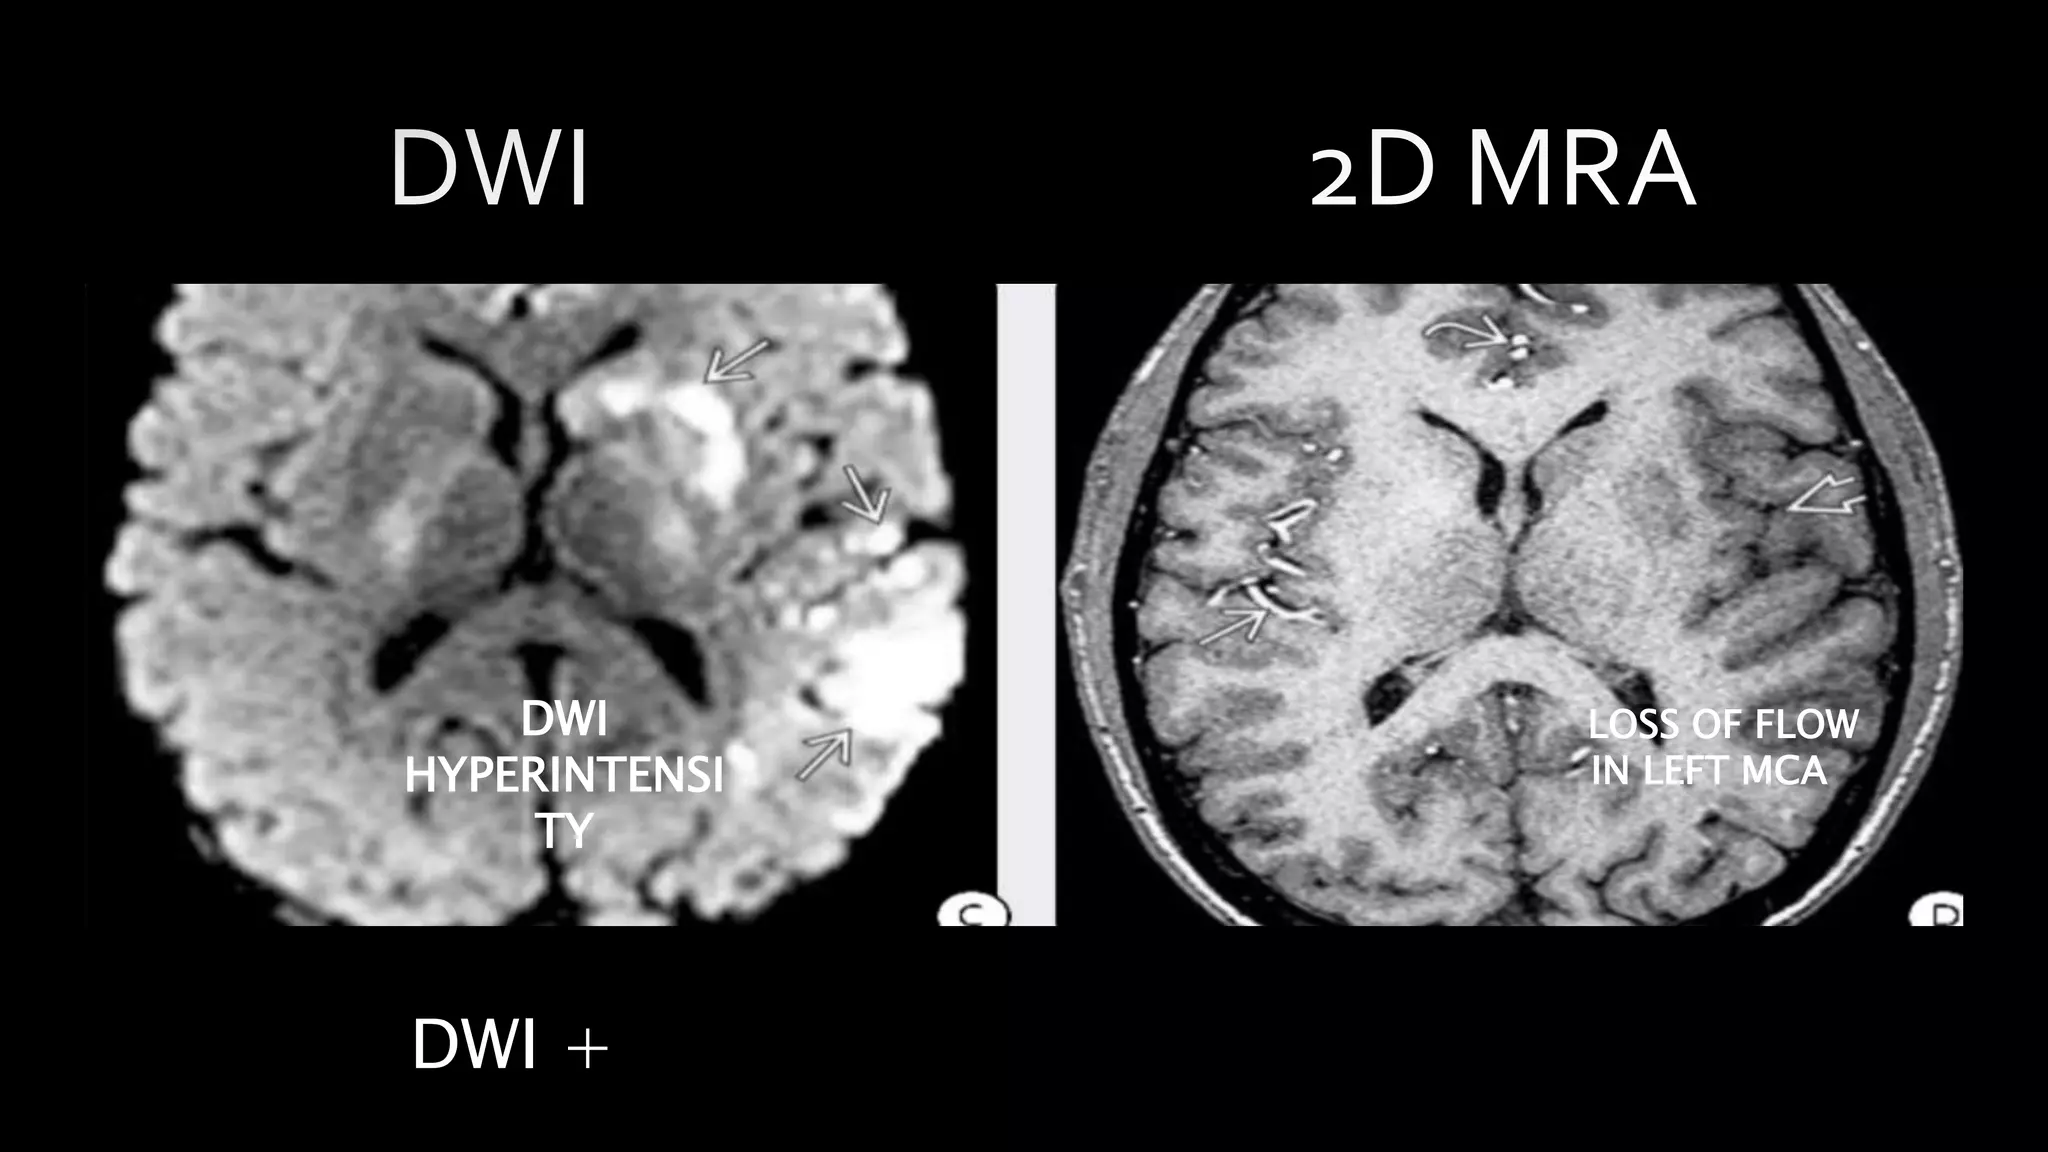

FLAIR +

PATCHY

HYPERINTENSITY LINEAR HYPOINTENSITY

IN LEFT MCA

DWI +

DWI

HYPERINTENSI

TY

LOSS OF FLOW

• #52 DWI of the same patient shows multiple patchy foci of diffusion restriction consistent with ACUTE CEREBRAL INFARCTION. AXIAL 2D MRA shows no flow in the left MCA